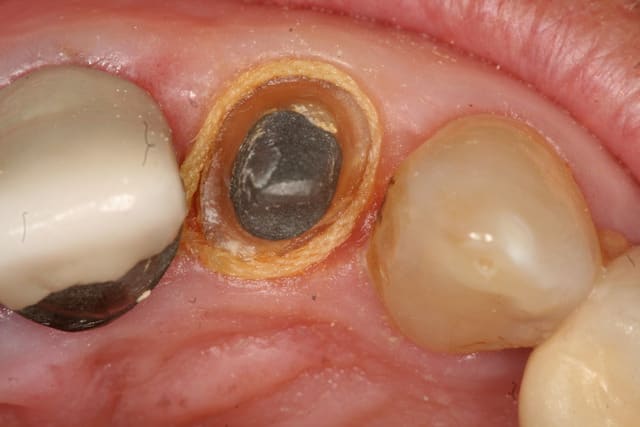

le jaune je sais faire

2010.04.positdental - Eugenol